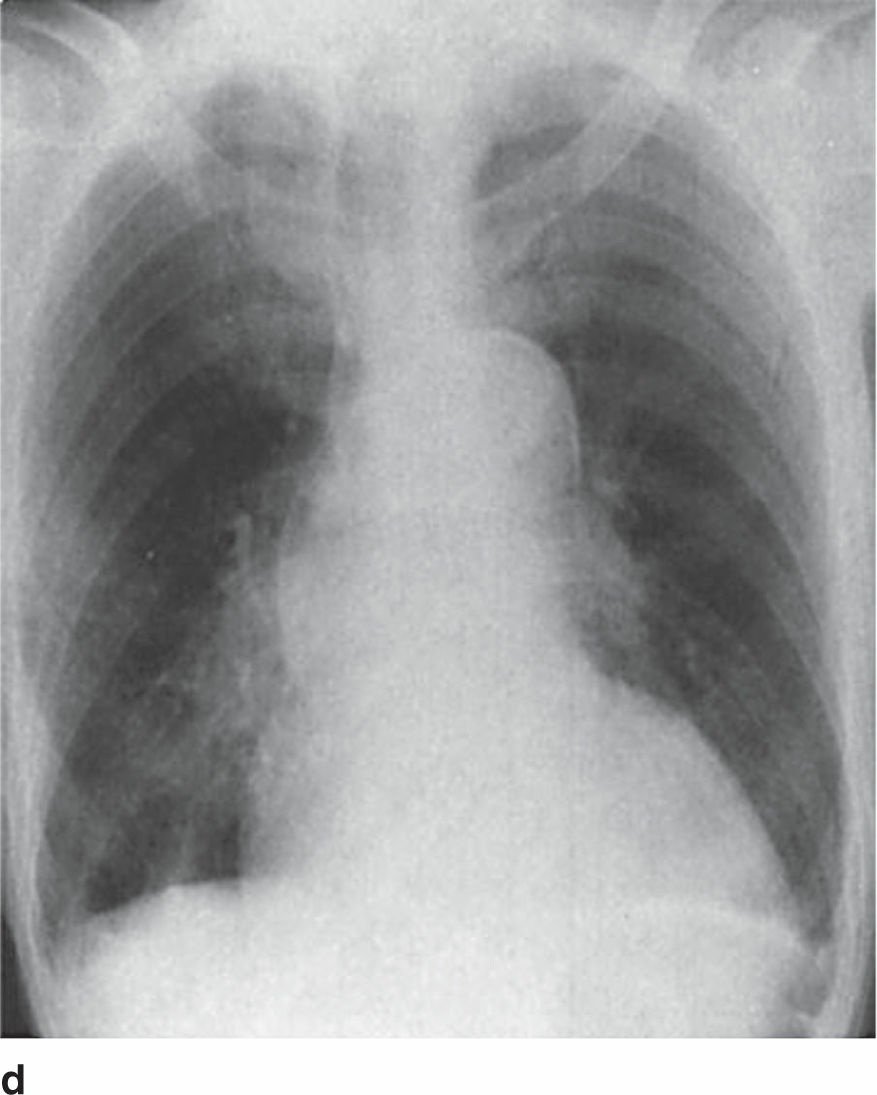

- Hình D: Bóng tim lớn dạng chiếc ủng, phù hợp phì đại thất trái – gợi ý bệnh lý tim mạch mạn tính.